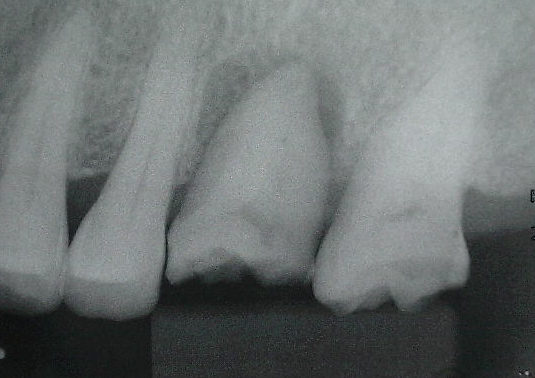

移植後

左下の親知らずを移植。

数週間開けて根管治療を行います。

補綴後

数カ月経過観察後、状態も良くなってきたところで被せ物を入れました。

(X線より周りの骨も回復してきたのが分かる)